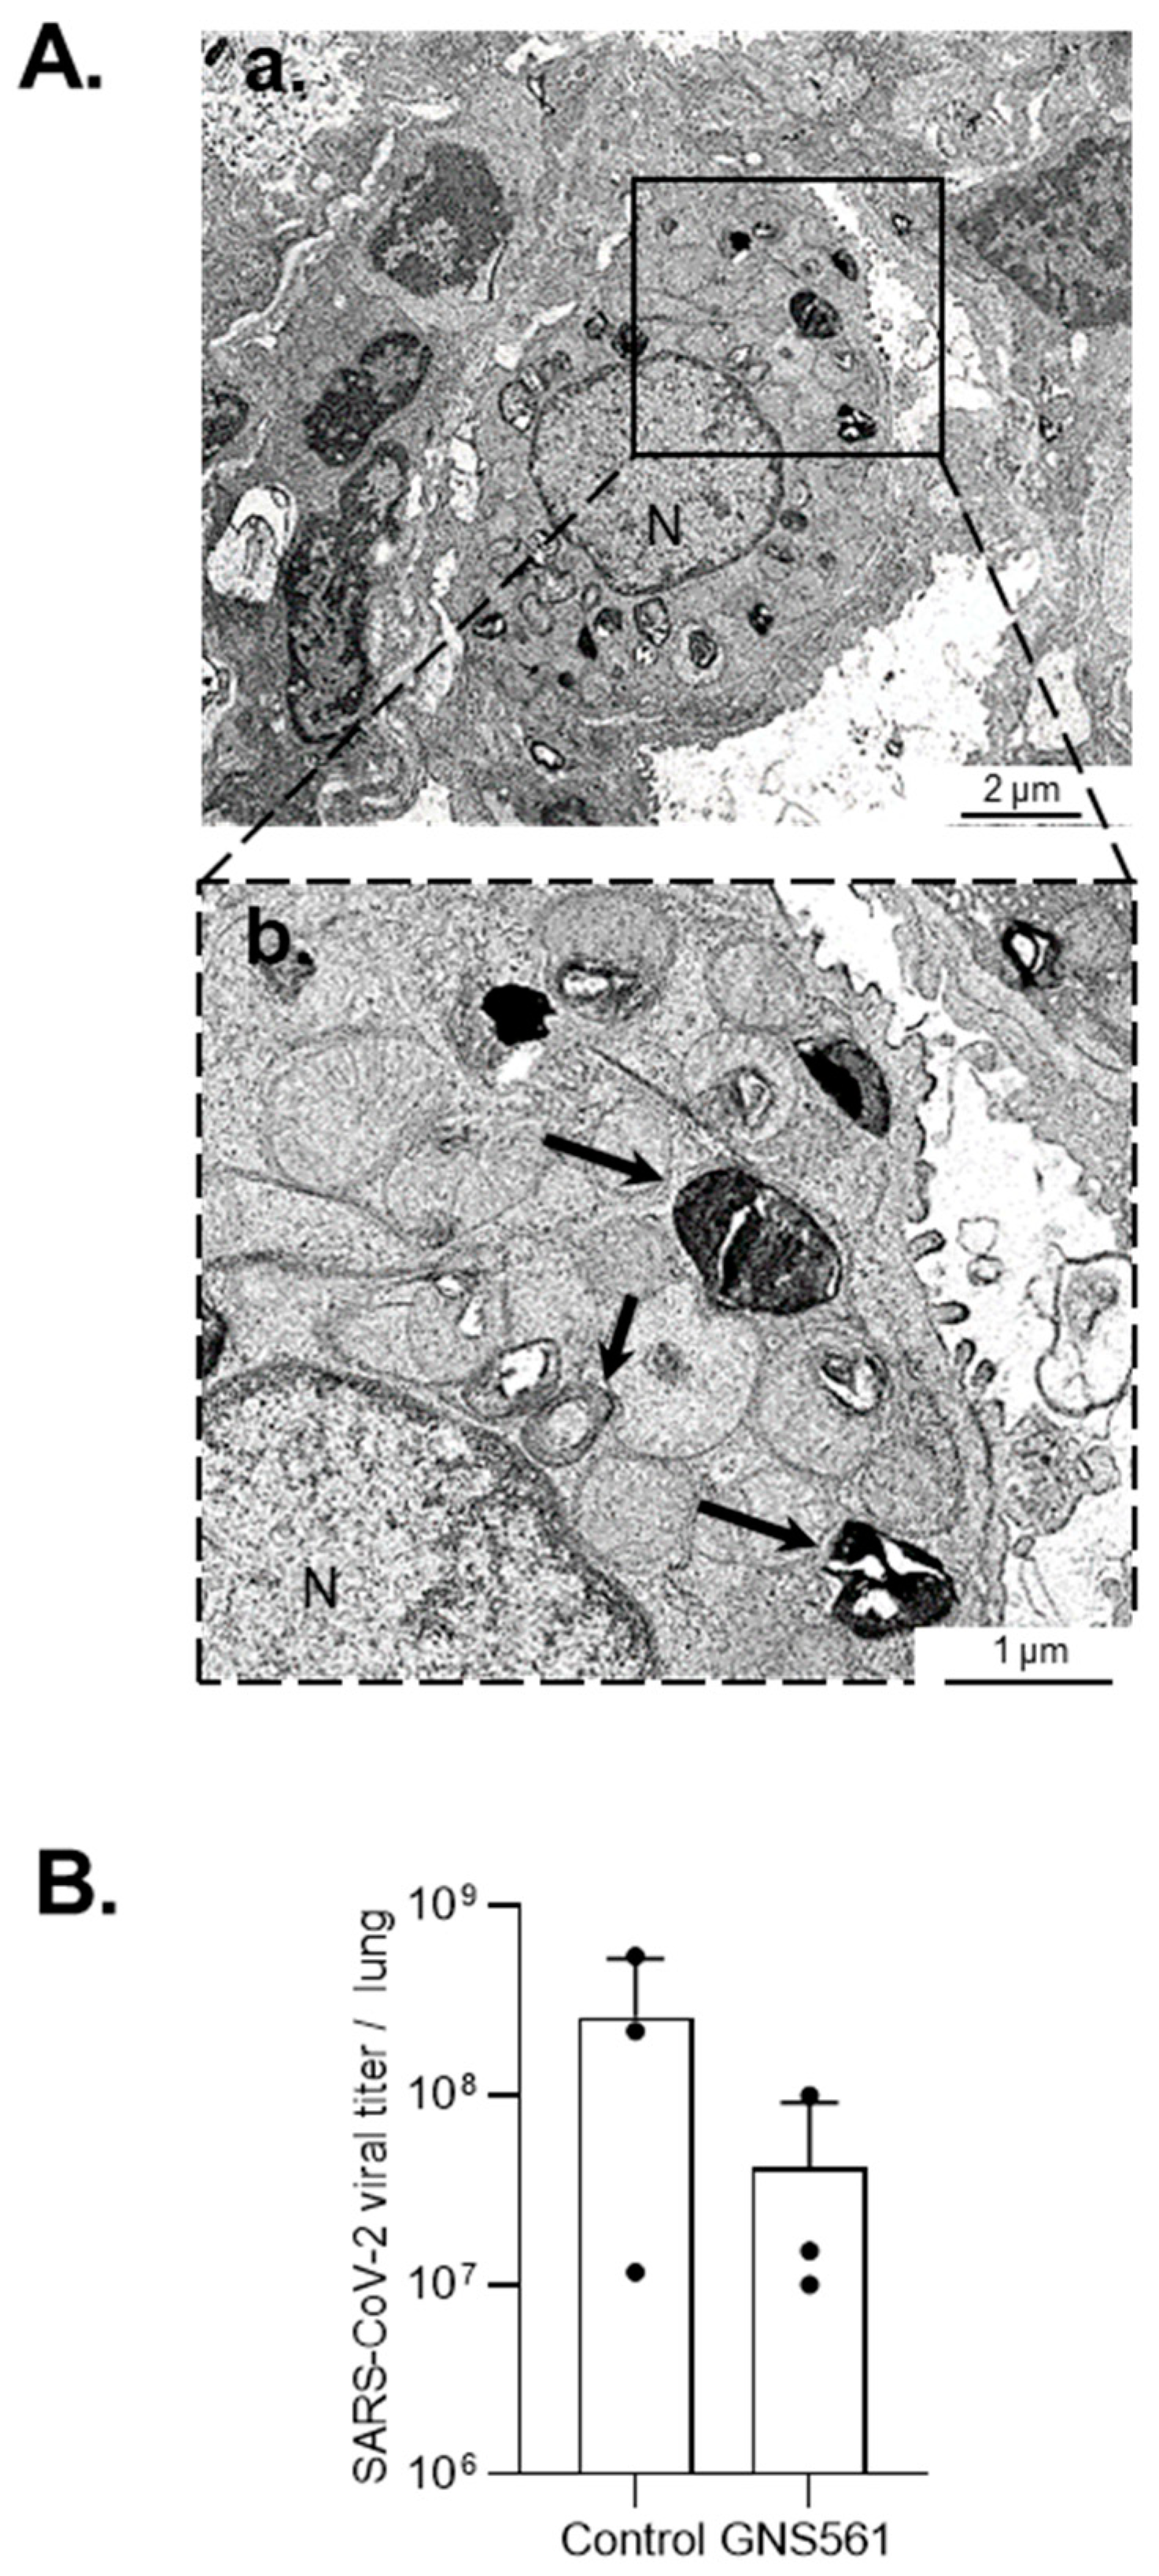

3.2. GNS561 Disrupts the Autophagy Mechanism during SARS-CoV-2 Infection